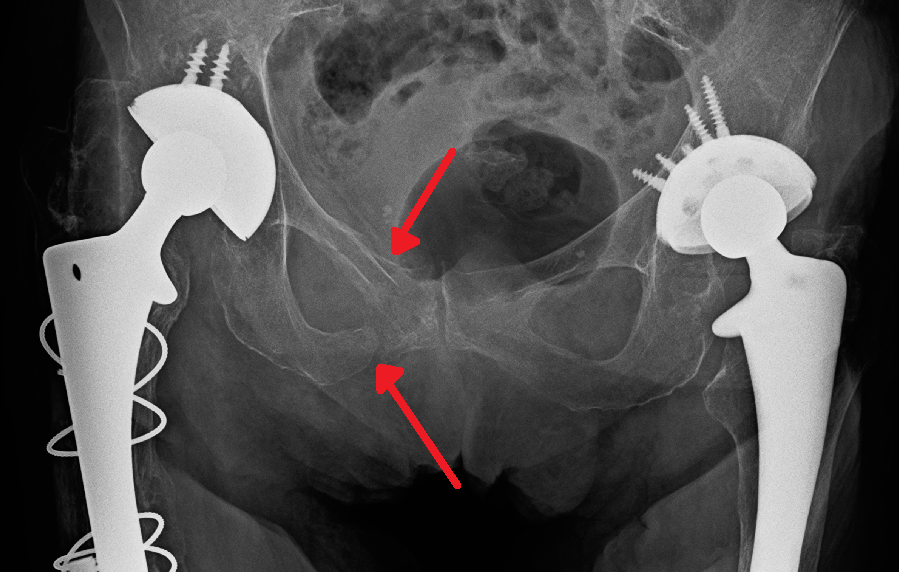

자동차 사고와 다층 건물에서의 추락은 둔기 외상의 가장 흔한 원인이며, 따라서 골반 부상은 다른 부위의 추가적인 외상과 흔히 연관되어 있다.[27] 특히 골반에서는 골반뼈, 상부 넙다리뼈, 엉덩동맥과 같은 주요 혈관, 요로, 생식 기관, 그리고 직장 등이 위험한 구조물이다.[27][30]

골반 골절은 가장 중요한 우려 사항 중 하나이며, 이는 출혈, 요도 및 방광 손상, 신경 손상을 포함한 수많은 합병증과 관련이 있다.[28] 골반 외상이 의심되는 경우, 응급 의료 서비스 직원은 환자의 골반을 안정시키고 환자를 병원으로 이송하는 동안 이러한 구조물의 추가 손상을 방지하기 위해 골반 결합기를 착용할 수 있다. 응급실에서 외상 환자를 평가하는 동안 골반의 안정성은 일반적으로 골절이 발생했는지 여부를 결정하기 위해 의료 제공자에 의해 평가된다. 의료 제공자는 골절을 감지하기 위해 X-ray 또는 CT 스캔과 같은 이미징을 주문할 수 있지만, 생명을 위협하는 출혈에 대한 우려가 있는 경우 환자는 골반 X-ray를 받아야 한다.[29] 환자에 대한 초기 치료 후, 심각한 골절의 경우 수술적 치료가 필요할 수 있으며, 일부 경미한 골절은 수술 없이 치유될 수 있다.[27]

생명을 위협하는 우려는 출혈이며, 이는 대동맥, 엉덩동맥 또는 골반의 정맥 손상으로 인해 발생할 수 있다. 골반 외상으로 인한 출혈의 대부분은 정맥 손상으로 인한 것이다.[28] 외상 후 종종 수행되는 FAST 스캔 동안 초음파를 통해 골반에서 체액(종종 혈액)이 감지될 수 있다. FAST 스캔에서 명백한 혈액이 없는 상태에서 환자가 혈역학적으로 불안정한 것으로 보이면, 후복막강으로의 출혈, 즉 후복막 혈종에 대한 우려가 있을 수 있다. 출혈을 멈추기 위해서는 위치 및 심각성에 따라 혈관 내 중재 또는 수술이 필요할 수 있다.[30]

골반 둔기 외상의 경우, X-ray나 CT 스캔을 통해 골절 여부를 확인하고, FAST 스캔을 통해 골반 내 출혈 여부를 확인한다.[29][30]